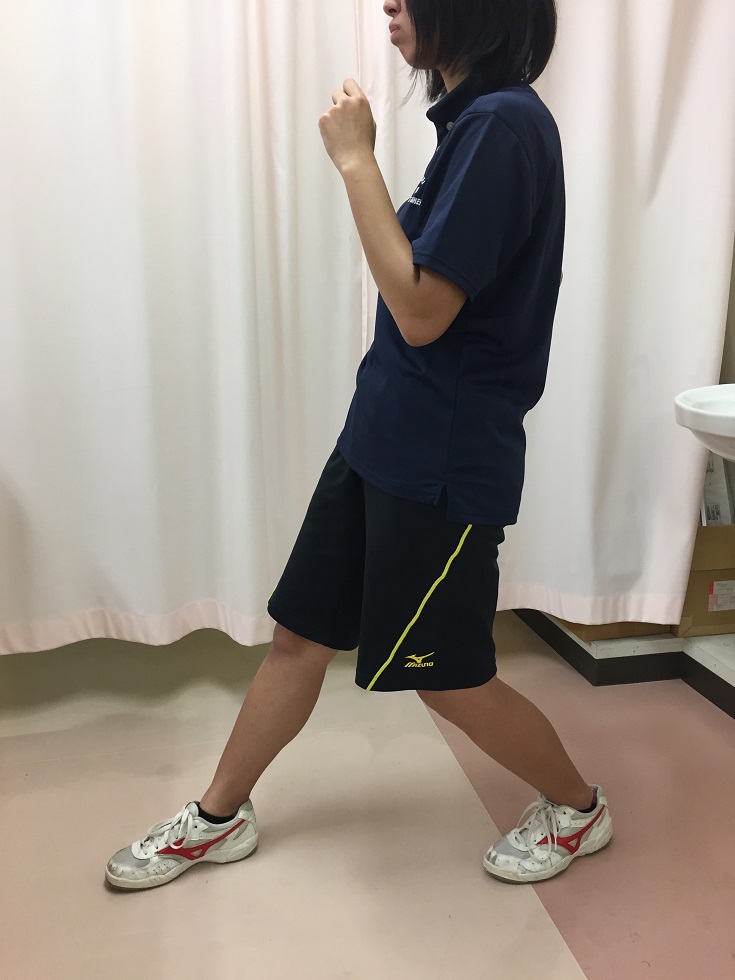

サイドステップ

ハーキーから横に移動します。移動する方向の足を踏み出したらすぐに反対の足を引きつけます。その時、つま先と膝は常に前方を向いているようにします。脚を引きずるようなステップやステップが大き過ぎると膝外反の原因となるので行わないようにします。

ステップ幅が大きいと方向の膝が外反しやすくなる